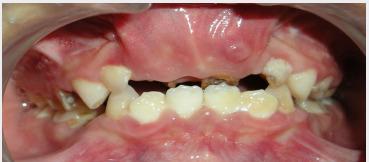

8-year-old boy with clinical diagnosis of CSS presented facial dysmorphism, sparse hair, a flat and wide nose, absence of nails on 3rd and 5th fingers of the right hand and 3rd and 4th fingers of the left hand, malformation of the feet, toes with nail hypoplasia. Oral and dental anomalies included : bilateral complete cleft lip and palate, delayed eruption of permanent teeth, presence of supernumerary tooth and taurodontism in the first permanent molars.

一名 8 岁男孩被临床诊断为 CSS,表现为面部畸形、稀疏的头发、扁平而宽的鼻子、右手第三和第五指以及左手第三和第四指无指甲、足部畸形、脚趾指甲发育不全。口腔和牙齿异常包括:双侧完全唇腭裂、恒牙萌出延迟、存在多生牙和第一恒磨牙尖牙畸形。